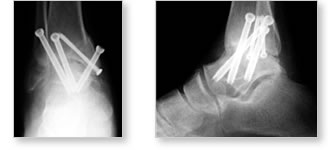

Arthrodesis is defined as the surgical fusion of a joint. Triple arthrodesis involves the fusion of the calcaneocuboid, talonavicular, and talocalcaneal ( i.e. subtalar) joints in the hind foot with bone graft material and internal fixation ( e.g. cannulated screws, bone staples).

Today, orthopaedic surgeons perform triple arthrodesis procedures for correction of marked varus or valgus deformities from residual clubfoot, cerebral palsy, and Charcot's joint disease (i.e. neuropathic arthropathy of hind foot); chronic acquired flatfoot from end - stage posterior tibial tendon ruptures;arthritis and arthritic conditions of hind foot.